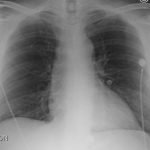

Chest x-ray and CT angiogram was performed to evaluate his thoracic and abdominal vasculature. Chest x-ray did not show any significant widening of the mediastinum. The CT angiogram demonstrated an intimal tear along the aortic arch separating a true and false aortic lumen, consistent with an acute aortic dissection. The true lumen (highlighted in blue in images 1-5) can be identified by continuity with an undissected part of the aorta1. While the false lumen (highlighted in red in images 1-5) can be identified by its crescent shape and larger cross-sectional area.1